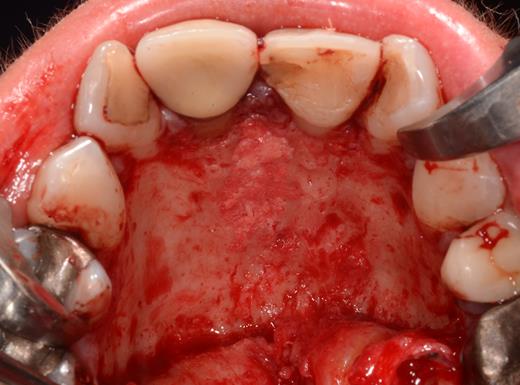

After a sulcular incision on the palatal side from teeth 15 to 25 and an incision in the midline of the palate omitting the incisive papilla and the two orifices of the NPD, two full-thickness mucoperiosteal flaps were raised. Thereafter, the incisive papilla and the whole contents of the incisive canal were enucleated (Figs 4–6). The bony incisive canal was filled with autologous bone harvested from the palatal region (bone scraper) (Fig. 7). A tension-free primary wound closure was achieved by moving the palatal flaps to the midline using single button and interdental vertical mattress sutures (Monocryl 4-0, Ethicon, Johnson & Johnson, USA) (Fig. 8). To avoid wound dehiscence and hematoma, an iodoforme gauze and a palatal plate were applied (Fig. 9). The patient was instructed to rinse three times a day with 0.1% chlorhexidine (formula hospitalis) for 2 weeks postoperatively. Sutures were removed after 14 days.

Preparation of the soft tissue of the incisive canal and the incisive papilla.